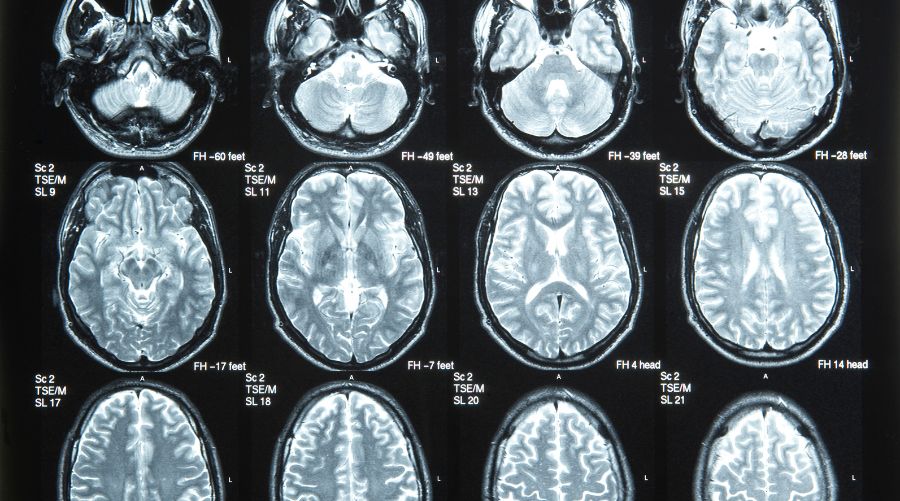

En imagen médica, las redes neuronales convolucionales analizan radiografías, resonancias o tomografías y diferencian lesiones sospechosas con una sensibilidad comparable a la de un radiólogo experto. Al mismo tiempo, su integración con técnicas como la biopsia líquida potencia la detección de mutaciones en sangre, ofreciendo un método menos invasivo y capaz de monitorizar la enfermedad en tiempo real. Este enfoque incrementa la eficacia en la identificación temprana de recaídas y mejora el seguimiento del paciente.

- La integración de datos de imagen con registros clínicos también ha demostrado gran valor. Redes convolucionales analizan imágenes de tumores y las correlacionan con evolución clínica, generando modelos predictivos sobre la progresión de la enfermedad. Esto ofrece una herramienta de apoyo a los comités multidisciplinares, facilitando decisiones terapéuticas más fundamentadas.